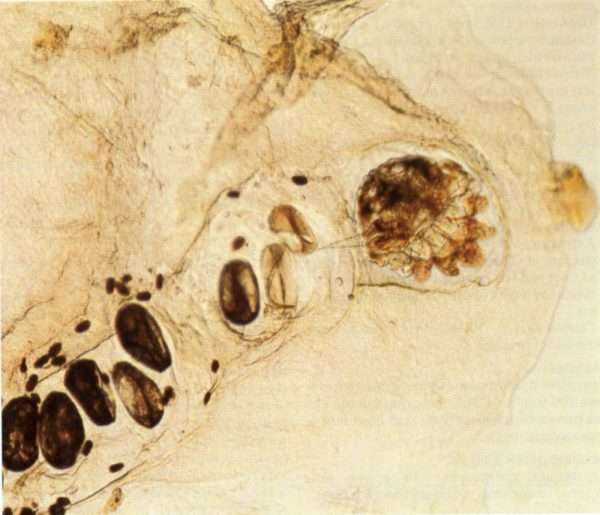

Чесотка возникает при поражении кожных покровов чесоточным зуднем. Возбудитель заболевания, называемый специалистами Sarcoptes scabiei, относится к отряду паукообразных. Размер самок паразита составляет 0,5-0,6 мм, продолжительность жизни в среднем около 1 месяца. Самцы гораздо меньше, всего 0,2-0,3 мм в длину.

Паразитирует клещ в верхнем слое кожи человека. После оплодотворения, самцы практически сразу погибают. Самки роют в толще кожных покровов ходы, откладывая 2-3 яйца в сутки. Спустя 2-4 дня появляются личинки, которые также могут создавать чесоточные ходы.

Активно питающиеся личинки спустя 3 дня линяют и становятся протонимфами, которые после второй линьки на 7 сутки превращаются в телеонимфы. В среднем процесс созревания паразита во взрослую особь занимает 2 недели. Вызвать заболевание может чесоточный зудень на любой стадии развития, но в подавляющем большинстве случаев чесотку порождают половозрелые клещи.

Диагноз чесотка выставляется врачом дерматовенерологом на основе данных жалоб и анамнеза, визуального осмотра, проведенных проб и лабораторных исследований. Окончательный диагноз выставляется только при обнаружении половозрелых клещей или их яиц на коже больного.

• Извлечение самого взрослого чесоточного зудня специальной тонкой иглой со слепого конца суточного хода. Данный метод применим только на недавно сформированных чесоточных ходах со свежей, не разрушенной папулой.

• Под контролем увеличительного стекла, специалист может выскоблить чесоточный ход специальной глазной ложечкой и исследовать полученный материал с помощью микроскопа.

• Метод тонкого среза. На папулу наносится 1 капля растительного масла, затем форменный элемент сыпи срезается скальпелем и переносится на предметное стекло. Из полученного среза готовят препарат и изучают его при многократном увеличении микроскопа. При использовании данного способа, можно обнаружить яйца клещей, личинок и взрослых особей паразита.